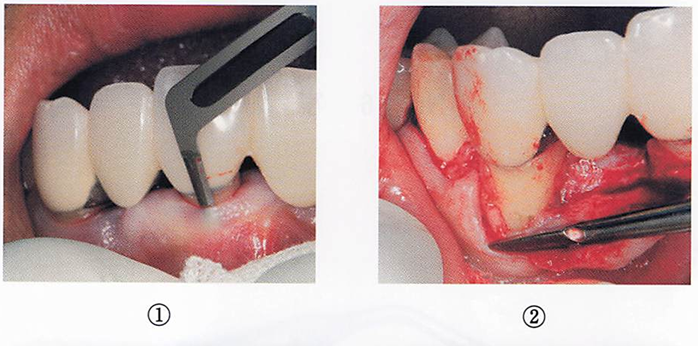

フラップ手術の手順の口腔内写真を別に示す。 粘膜骨膜剥離をしているのはどれか。1つ選べ。

a. ①

b. ②

c. ③

d. ④

解答を見る

b